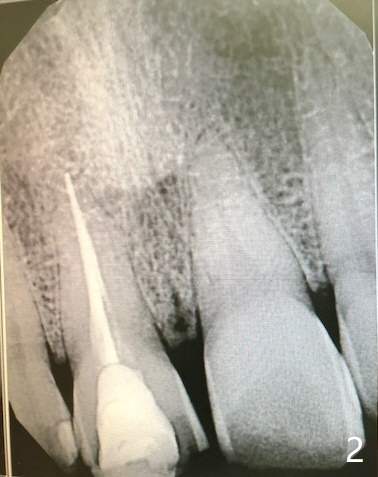

A 55-year-old man have several missing teeth with #8 crown subgingival fracture and #15 mobility (Fig.1,2). It suggests heavy occlusion. A long implant is expected. If osteotomy remains palatal, place an IBS implant (3.5 or 4.0x13 mm). Also prepare UF for cosmetics and longer implant. The bone at #15 should be low, a good indication for IBS implant at the later stage.